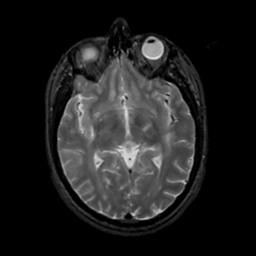

MR Study #7, March 24, 1991 -- Slice #23